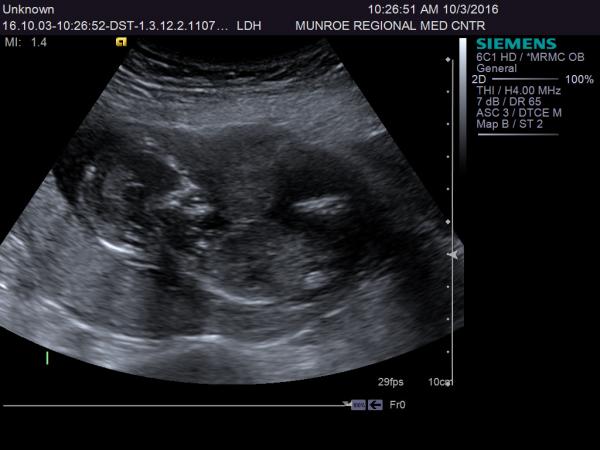

my cousin is 14 weeks 5 days and had an ultrasound today but the tech wouldn't look at gender....so what do you think?Attachment 33252Attachment 33253